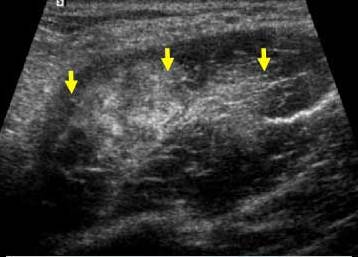

Ingrosare hiperecogema – stadiul 2 Rodineau

Echivalentul stadiului II al lui Rodineau se caracterizeaza prin

Fie o ingrosare focalizata, hiper ecogena,

centrala, sau a aponevrozie peri musculare

Fie de o dezorganizare mio-arhitecturala, care este inlocuita de

o zona cel mai frecvent hiper-ecogena

heterogena. Cautarea leziunilor mici este favorizata de miscari de contractie musculara